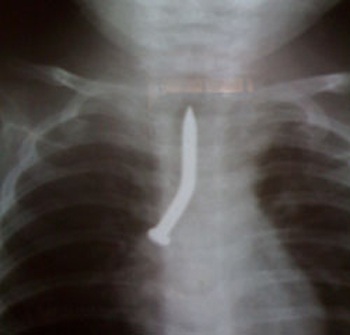

Hình ảnh chiếc đinh nằm trong phổi bé T qua chụp X-quang

Tại khoa Tai Mũi Họng - BV Nhi Đồng 1, bé được soi cấp cứu và đã gắp ra một cây đinh dài 3,5cm nằm lọt vào phế quản gốc bên phải. Sau 7 ngày điều trị bé đã được xuất viện.